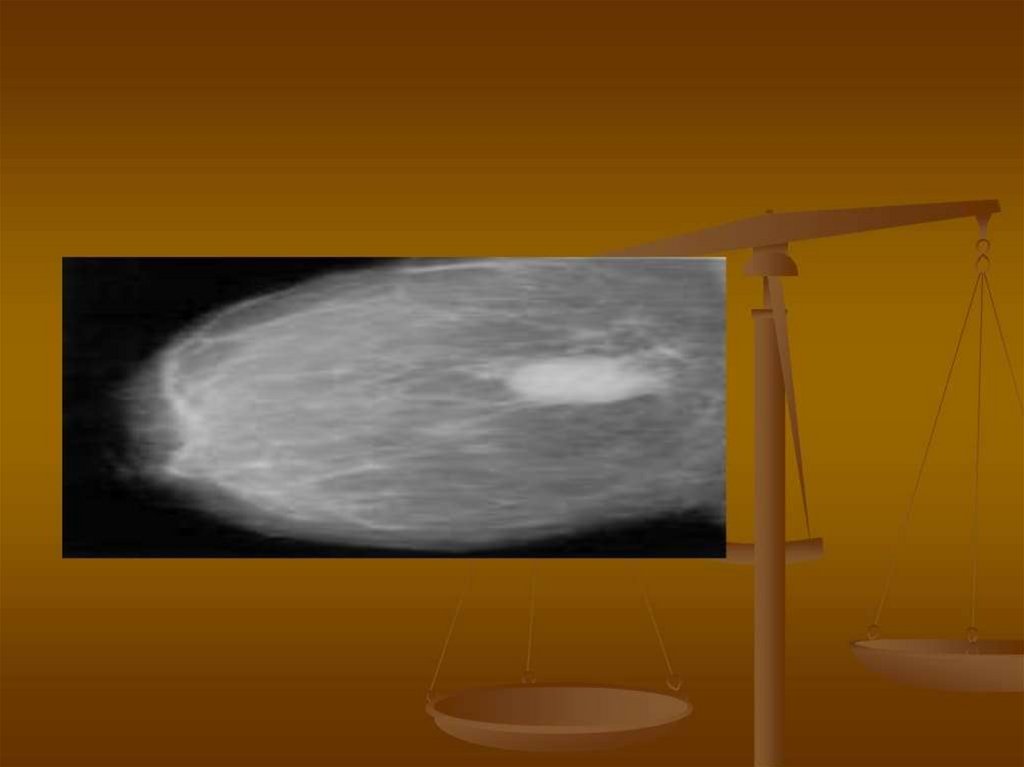

Benign Breast Disease